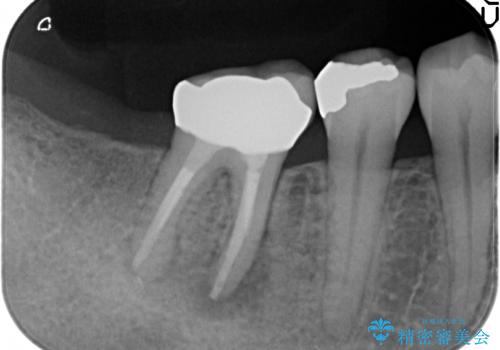

- 銀歯がしみることを主訴に来院されました。

銀のつめものを除去したところ、大きなう蝕を認めました。

咬合力が強いため、割れる心配がなく強度の高いPGA(ゴールド)インレーをご希望されました。